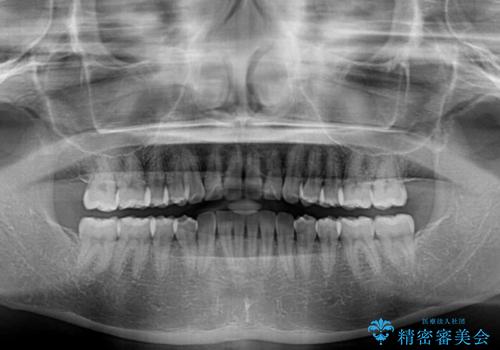

上下前歯のデコボコ ワイヤー装置で楽して改善

- 上下前歯のデコボコを気にして来院された患者様です。

ワイヤー矯正でもインビザラインでも、どの装置でも対応可能でしたが、安価で楽して素早く治療を終えたいとのことで、メタルブラケット装置による矯正治療を行うこととしました。

治療中は大きなトラブルもなく、予定の1年半でスムーズに治療を終えることができました。